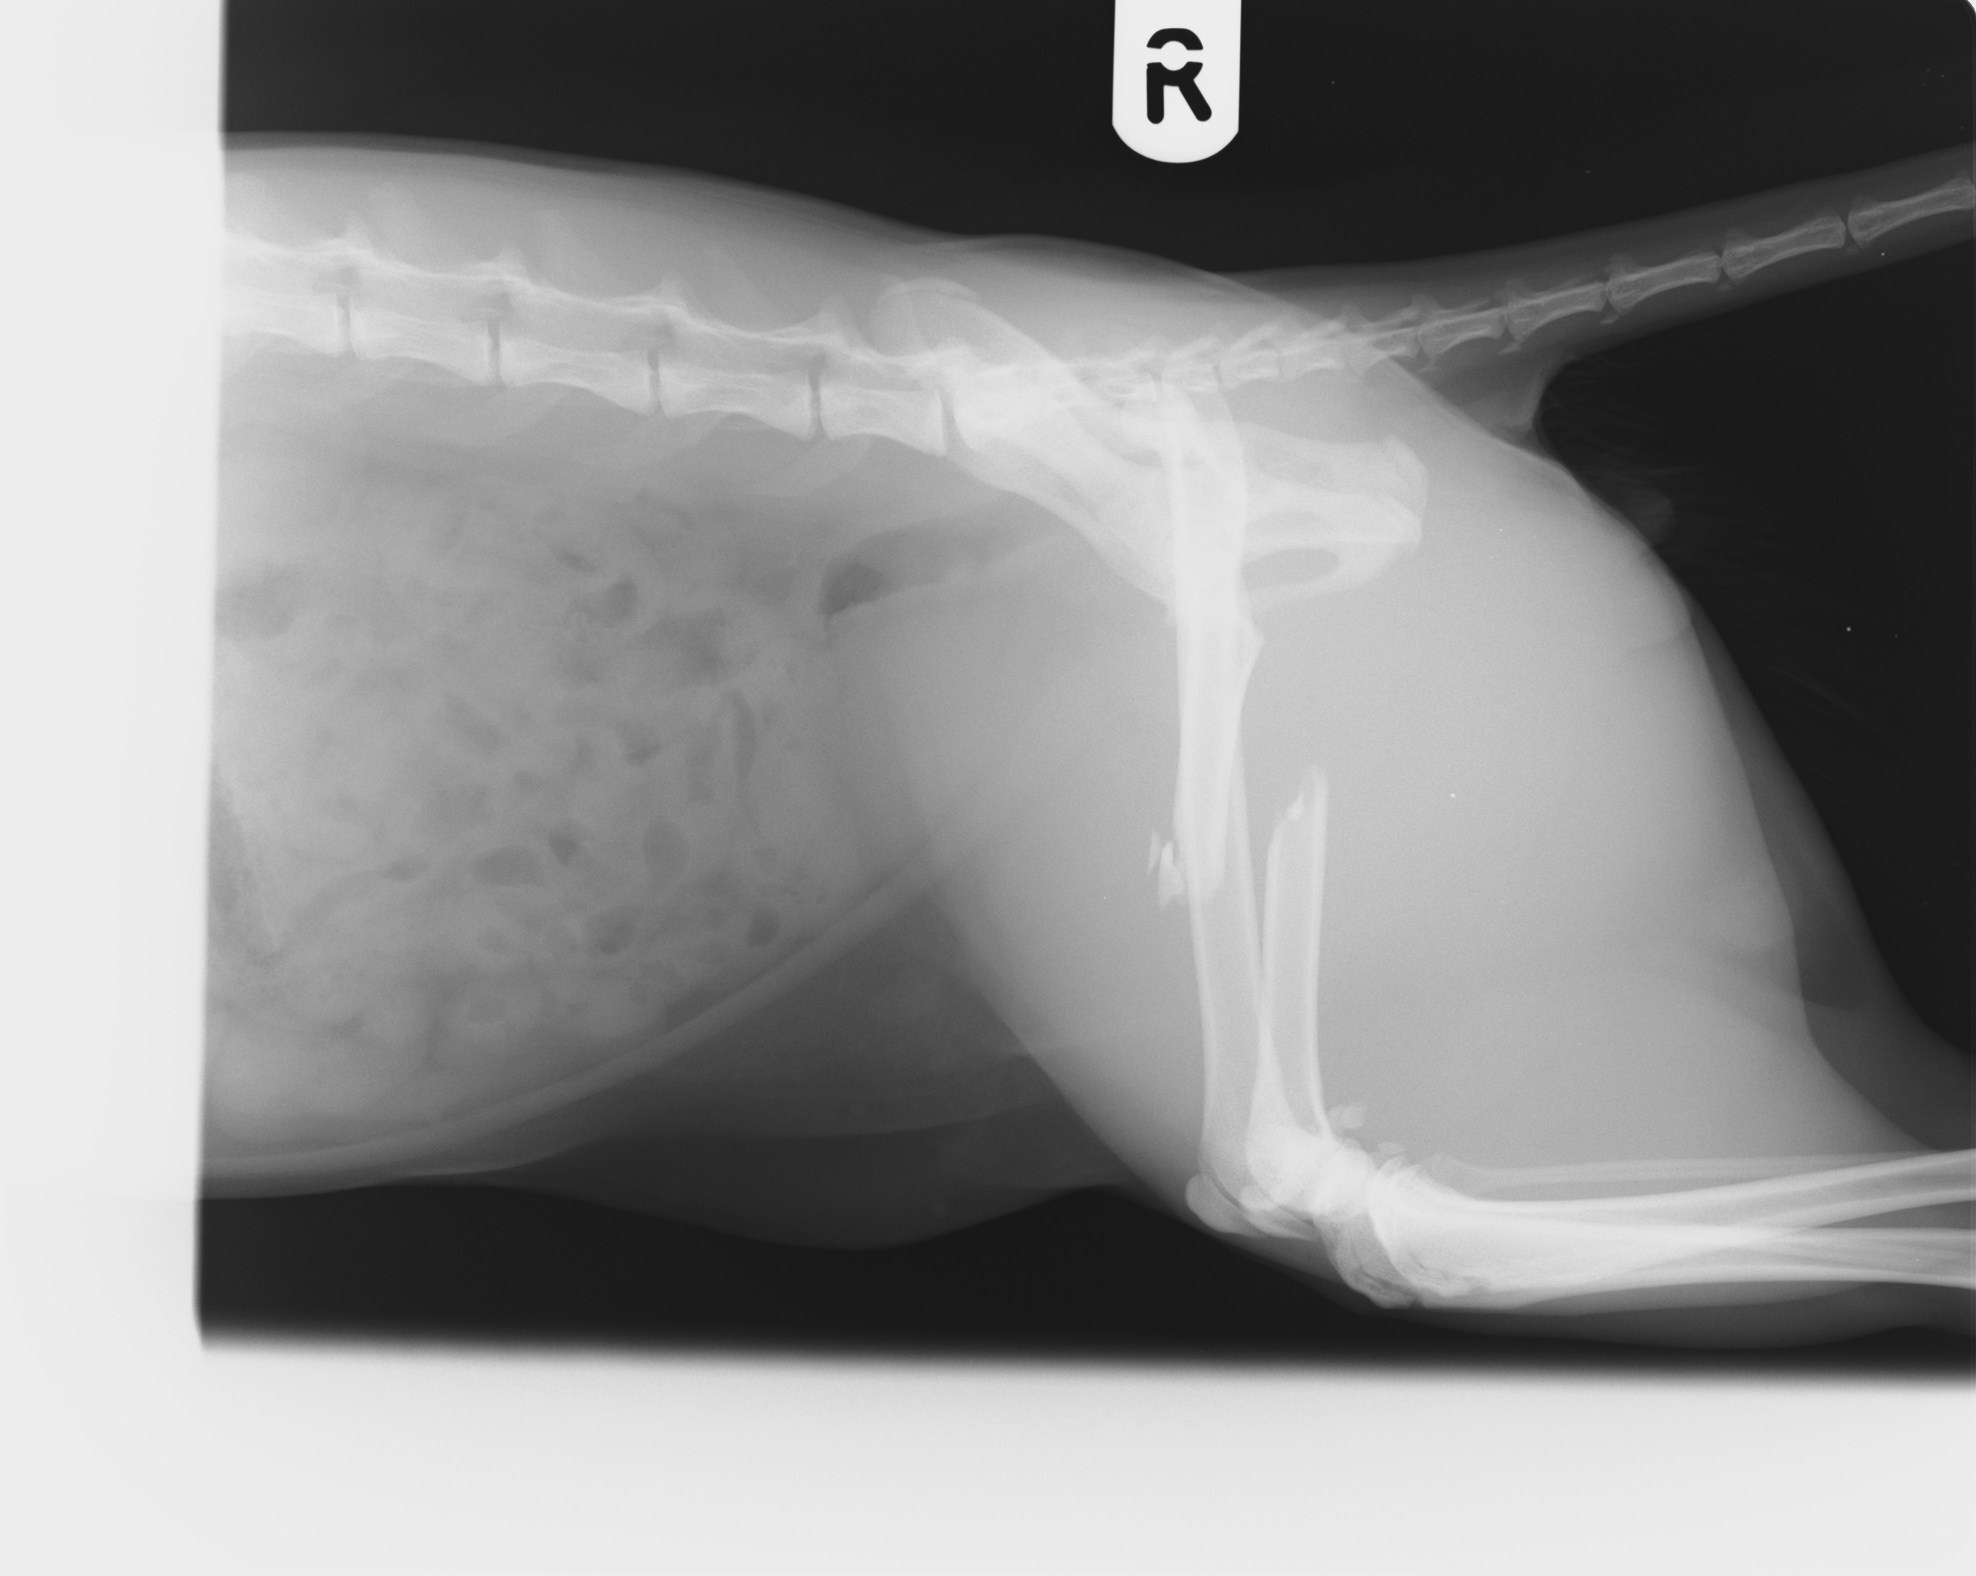

My name is Kaitlyn and I’m fundraising for our beloved cat, Sanza. He was recently hit and left on the side of the road near Shortlanesend. Sanza has serious injuries – his hip is dislocated and his femur is broken. The vets have told us he needs urgent treatment if he’s going to walk and live a pain-free life again.